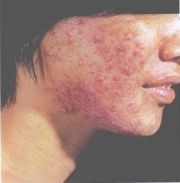

| 2021年7月26日 (一) 20:03 | 寻常痤疮.jpg (文件) |  |

24 KB | Uploaded with SimpleBatchUpload | 3 |